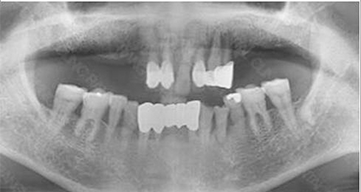

治療です。 前後写真

入れ歯の不快感を解消し、全顎インプラントを完成させます。

自然な機能と審美性の両方を満たす結果です。